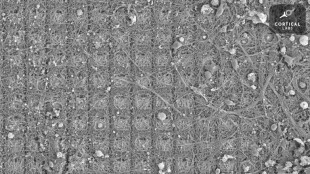

Des neurones doués de sensations ont appris à jouer à un jeu vidéo (étude)

Des neurones cultivés dans une boîte de Petri sont capables d'apprendre à jouer à Pong, le grand classique des jeux vidéo, faisant ainsi preuve d'un "comportement intelligent et doué de sensations", selon des chercheurs en neurosciences australiens.